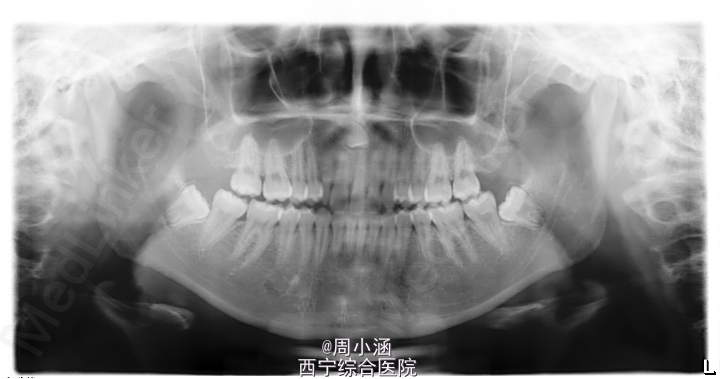

青年女患者,患者于1周前咨询正畸治疗,拍片发现上颌前部埋伏牙,建议拔除,今为进一步治疗来我院就诊,建议同期拔除38、48阻生牙

全景片示:11,21,根方可见一埋伏牙13,38,48近中阻生

1.右上前牙区埋伏牙13 2.38、48阻生齿

正畸患者,发现埋伏牙一般会拔除,其余偶然发现的,可能不予处理